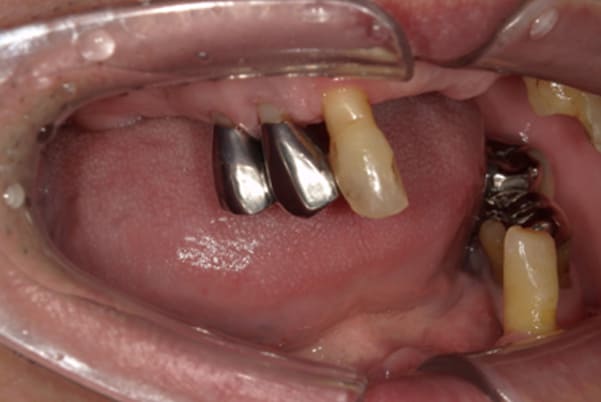

症例レポート[CASE.08]

娘とハンバーガーを食べたい

- 男性(50代)

- 娘とハンバーガーを食べたい、お肉も食べれるようになりたい、カラオケに行きたい

- 上顎精密金属床総入れ歯

- 下顎精密金属床総入れ歯

- 磁性アタッチメント(白金加金) 3歯

- 上顎精密金属床総入れ歯:55万円

- 下顎精密金属床総入れ歯:55万円

- 磁性アタッチメント:11万円×3歯

(白金加金)

合計:143万円(税込)

上下互い違いで咬む歯同士がない状態のため、柔らかいものを舌で潰され召し上がっておられました。

かみ合わせがなく、すれ違い咬合と言われる難症例に分類される状態でした。

上の歯は重度歯周炎でぐらぐらで、お痛みも繰り返しており、抜歯が必要な状態でした。

検査の結果、下の3本のうち、2本は何とか根は残せる状態であったため、虫歯の治療、根の治療を行い残すことに努めました。

上下の歯同士のかみ合わせがない状態で長年過ごされていましたので、当初はどこで咬んだら良いかわからない状態でしたが、治療用入れ歯を用い、調整を行い、本来のかみ合わせに戻すことが可能になりました。

初めての入れ歯が総入れ歯の場合は、大きな違和感を感じられる方が多いですが、上顎に金属を用いた入れ歯にすることで、厚みを薄くし違和感を抑え、お食事での温熱も感じられるようになりました。

下の総入れ歯は外れやすいため大きな虫歯はありましたが、虫歯治療を行い、根のみ残せた2本の歯に磁石を利用することで歌われた際も外れない入れ歯の設計としました。

下顎は舌があるため、上顎と比較すると総入れ歯の場合、外れやすい傾向があります。患者様はまだお若く、お肉がお好きだったとのこと、またお歌もご趣味とのことで、ご相談の上、なるべく外れない設計としました。

磁石を用いた入れ歯の設計により上下の入れ歯は、お食事やお歌を歌われ大きなお口を開けても外れない状態が可能になりました。

当初、ハンバーガーを召し上がりたいと仰っていましたが、今ではステーキも召し上がられ、カラオケでも入れ歯は外れず、滑舌が全く変わったと喜んで下さりました。